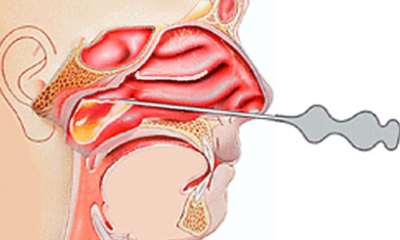

Прокол при гайморите

Прокол может служить методом диагностики. Так же для облегчения выхода гноя проводится хирургическое вмешательство. Как делают прокол при гайморите (фото 4): в носовую пазуху предварительно закладывают вату, смоченную лидокаином для анестезии, затем тонкой иглой производится прокол через средний либо нижний ход. При помощи шприца удаляется гной. Прокол при гайморите не относят к сложным операциям, поэтому осложнения возникают крайне редко.